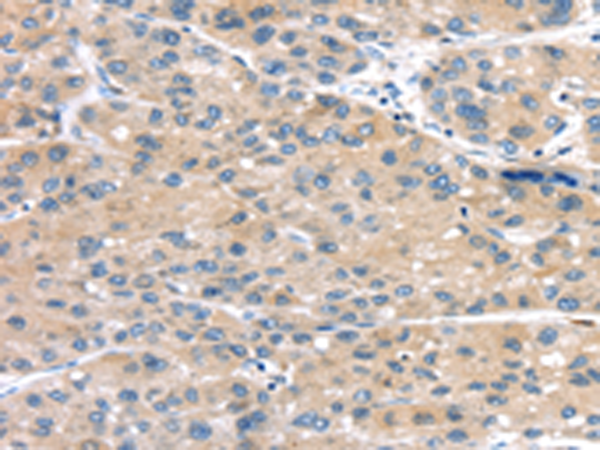

分类: 科研抗体货号: P11013别名: ASK1, MEKK5, MAPKKK5应用: IHC反应种属: Human, Mouse